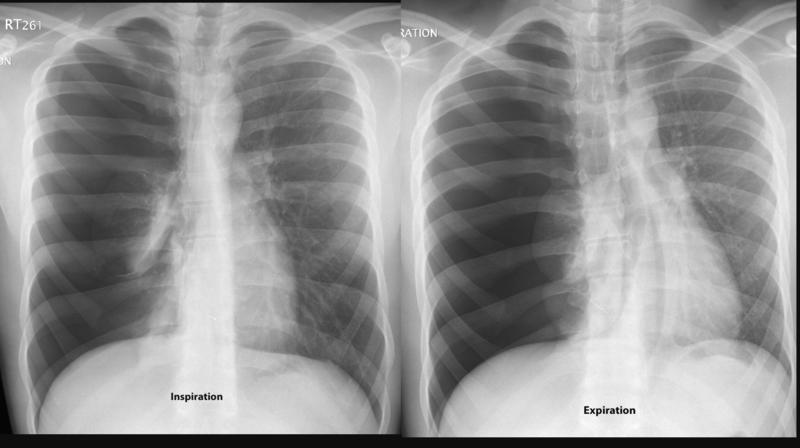

Pneumo insp/exp (similar - mild tension)

Pneumo insp/exp

(similar - mild tension)